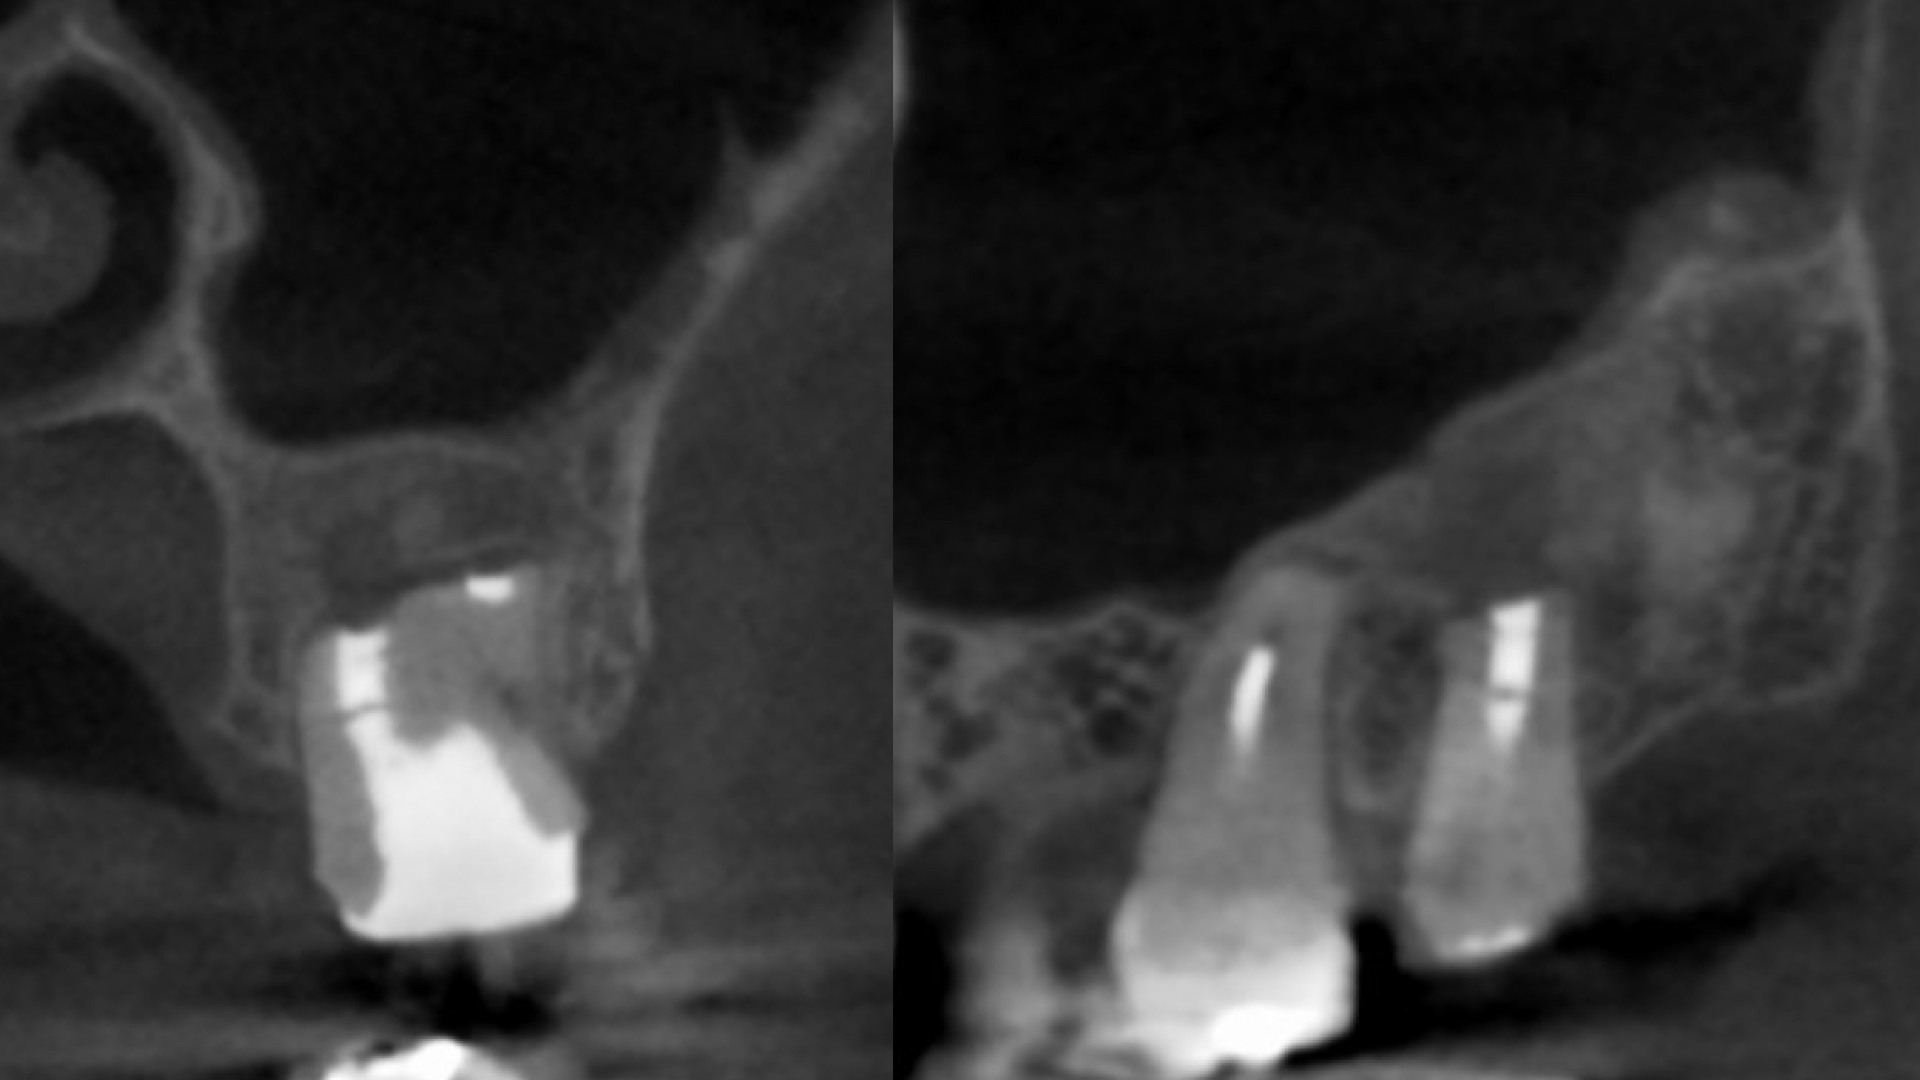

CT(3次元レントゲン)診査

- 歯の状態:歯質が骨縁上に適切な厚みを持って存在する。根尖の外部吸収様所見

- 上顎洞炎を伴う根尖性歯周炎

- 歯根の外側に病原の可能性があり外科的対応を治療計画に組み込む必要がある。

- 根尖部での外部吸収により根尖の拡大を認めるため細菌の押し出しに配慮した手技が求められる。

- 上顎洞炎の消失を確認するため6ヶ月以上の経過観察を必要とする。

- 外科処置の際は、歯の破折を考慮する。